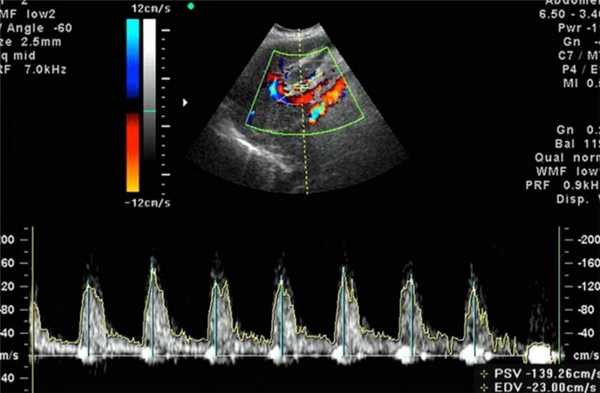

Исследование проводится лежа на спине, так же, как и УЗИ 2-3 триместра, в том же кабинете, тем же датчиком. Если Вы не можете долго лежать на спине, у Вас появляется головокружение, нехватка воздуха, ни в коем случае не терпите, сразу скажите об этом специалисту УЗД. При выраженном синдроме сдавления нижней полой вены допускается оценка кровотока в положении лёжа на боку. На живот наносят специальный гель, по которому и будет двигаться ультразвуковой датчик. При проведении Допплерометрии на экран аппарата в режиме ЦДК выводятся интересующие сосуды, окрашенные в красный или синий цвет в зависимости от направления тока крови к датчику или от датчика. Затем появляется графическое изображение скорости тока крови в течение сердечного цикла в виде двух-трехфазной кривой и слышно характерное для каждого сосуда звучание. Врач УЗД проведёт все необходимые измерения, в конце исследования всё подробно расскажет о его результатах и даст рекомендации. Как правило, исследование занимает не более 15 минут. Более подробно об оценке кровотока в системе мать-плацента-плод можно почитать и послушать по этой ссылке.

- Цветное картирование - состояние даже мельчайших сосудов и их проходимость кодируется цветом.

Оценка состояния кровоснабжения с помощью допплера формируется на основе следующих показателей:

- Систоло-диастолическое отношение - отношение максимальной и минимальной скорости кровотока;

- Индекс резистентности - отношение разницы максимальной и минимальной скорости кровотока к максимальной в период сжатия;

- Пульсационный индекс - отношение разницы максимальной и минимальной скорости кровотока к средней скорости за полный цикл сердца.

Систоло-диастолическое отношение в сосудах. СДО рассчитывается по формуле. Врач определяет соотношение максимальной скорости в сосуде в систолу и остаточной скорости - в диастолу. Показатель вычисляется для крупных сосудов матки, плода и пуповины. ДСО каждого сосуда меняется в зависимости от срока.

Норма СДО в артерии пуповины

Норма СДО в артериях матки в III триместре: 1,3-3,7

Индекс резистентности

ИР также рассчитывается по формуле. Гинеколог вычисляет отношение СДО к максимальной скорости движения крови в сосуде в систолу. Чем выше результат, тем хуже проходимость сосуда и тем больше сопротивление кровотока. Нормы УЗДГ при беременности по ИР зависят от сроков беременности, вида и диаметра сосуда.

1. Индекс резистентности в артериях матки в III триместре: 0,3-0,9.

2. Индекс резистентности в артериях пуповины:

| Срок, неделя | Индекс резистентности (ИР) |

| 16-19 | 0,78 |

| 20-22 | 0,74 |

| 23-25 | 0,71 |

Норма скорости кровотока в сосудах матки в III триместре в среднем: 60-71 см/секунду.

Пульсационный индекс

ПИ в III триместре должен составлять 0,4 -,64.